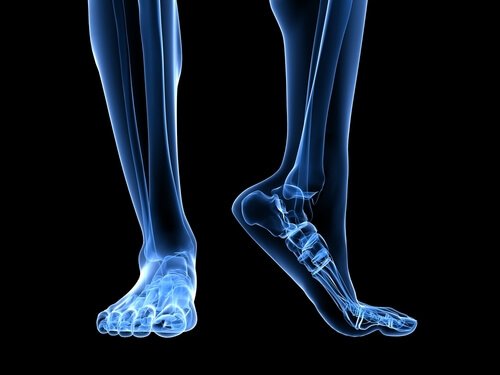

Заболяването плантарен фасцит е възпаление на плантарната фасция на крака, връзка, която свързва костта на петата с близките фаланги и се простира и свива с всяка стъпка, подобно на гумена лента.

Плантарната фасция е много широка, плътна тъкан поради огромното количество натиск и съпротива, което трябва да поддържа.

Има няколко анатомични структури, които играят роля при всяко претоварване на плантарната фасция.

Ахилесовото сухожилие е връзка, която свързва мускулите на прасеца, известни като прасци, и мускулите на ходилото до костите на петата. Притискането на ахилесовото сухожилие води до увеличаване на натиска върху петата на костта, което води до увеличаване на натиска върху плантарната фасция.

Друг фактор, който трябва да имате предвид в анатомичната структура, е ударът на крака, или с други думи, как кракът се докосва до земята. Плоските крака или крака, които имат тенденция за плоско стъпало разтягат плантарната фасция повече, като по този начин увеличават риска от разкъсване поради допълнителното притискане върху тъканта.